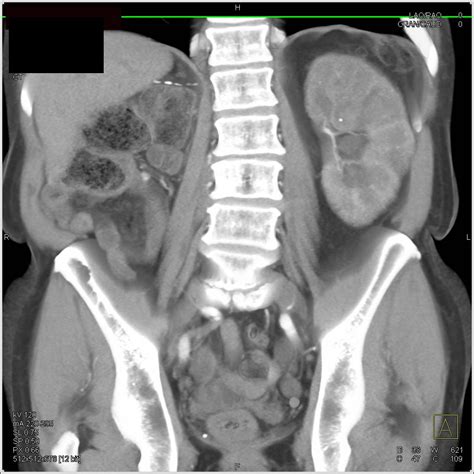

Diagnostic Imaging and Identification

While looking at pictures online provides a general idea, medical professionals use advanced imaging to identify renal calculi within the body. These diagnostic tools are far more accurate than a visual inspection alone.

Common diagnostic methods include:

• Non-contrast CT Scans: The gold standard for detecting stones, as they provide high-resolution images of the entire urinary tract.

• Ultrasound: A non-invasive method that uses sound waves to visualize stones within the kidney.

• KUB X-ray: A standard X-ray of the kidney, ureter, and bladder, though it may miss smaller, less dense stones.